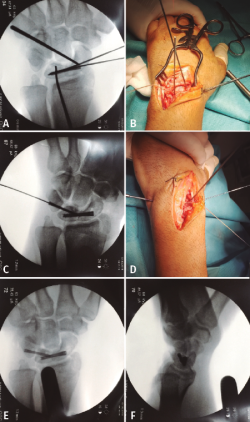

Bajo visión directa se corroboró la existencia de la lesión sospechada en las radiografías y TC prequirúrgicas, y una lesión no reparable del ligamento escafolunar. El hueso grande articulaba directamente con el radio, ocupando la fosa semilunar del radio. A continuación, se redujo el carpo, mediante tracción y flexión palmar forzada, acompañado de una presión directa del semilunar. Cruentación de todo el cartílago de las superficies articulares entre el semilunar y el escafoides, hasta conseguir exponer el hueso subcondral. A continuación, para ayudar en la manipulación y reducción de ambos huesos se colocaron 2 agujas de Kirschner a modo de joystick. Una vez reducidos, se realizó la osteosíntesis mediante tornillo Acutrak Mini®(Figuras 3A y 3B). En un segundo tiempo se retiró el cartílago articular de las superficies articulares entre el semilunar y piramidal. Se redujo con ayuda de una aguja de Kirschner y osteosíntesis con un Acutrak Micro®(Figuras 3C, 3D, 3E y 3F). En último lugar, se realizó una plicatura y cierre capsular mediante un implante Minilok®; se reforzó con puntos simples. Cierre de la 3.ª y la 4.ª correderas. Férula con inmovilización del primer dedo durante 8 semanas. Extracción del material de osteosíntesis a las 8 semanas. El objetivo de esta técnica (reduction and association of the scaphoid and lunate –RASL–) es conseguir una pseudoartrosis, cuya falta de consolidación consigue mejor control del dolor, amplitud de movimiento y fuerza de agarre que con una artrodesis exitosa(2,3).

Figura 3. A y B: osteosíntesis del semilunar y escafoides con Acutrack Mini®; C y D: osteosíntesis del semilunar y escafoides con Acutrack Micro®; E y F: resultado postoperatorio inmediato.